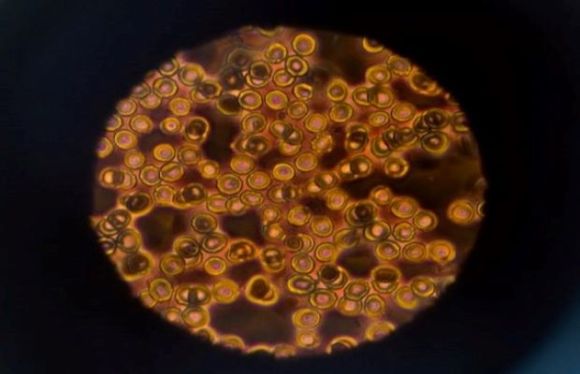

Our goal is to design microrobots for precision delivery of biochemical and cellular patterning for applications in personalized therapeutics, drug delivery and tissue engineering.